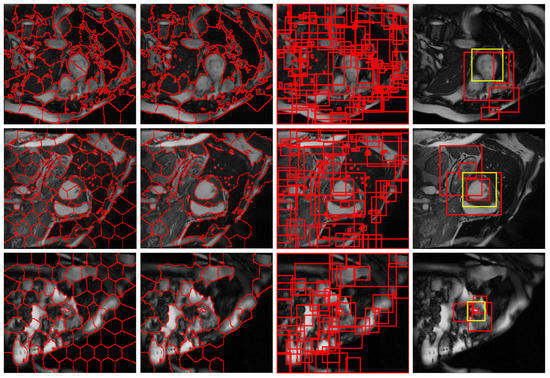

2.2. Candidate Region Proposal

2.2.1. Structural Similarity-Enhanced Supervoxel Over-Segmentation

2.2.2. Supervoxel Region Merging by Hierarchical Clustering